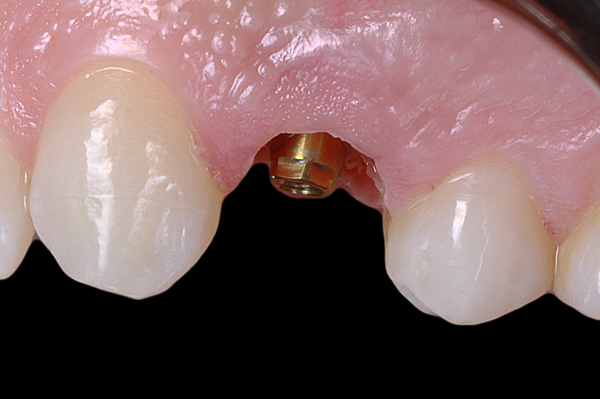

Il caso presenta la riabilitazione di un premolare superiore interessato dal fallimento di un trattamento endodontico in una paziente donna di 37 anni, non fumatrice e con una buona igiene.

A seguito dell'analisi radiografica viene pianificata l'estrazione atraumatica del premolare con l'inserimento contestuale di un impianto Shelta. La riabilitazione immediata viene eseguita con un pilastro XA per protesi avvitata, su cui viene fissato un provvisorio realizzato in laboratorio secondo i principi dei profili di emergenza della tecnica B.O.P.T.

Donna, 37 anni, non fumatrice, con una buona igiene, si presenta in studio con un fallimento del trattamento endodontico dell'elemento 1.4.